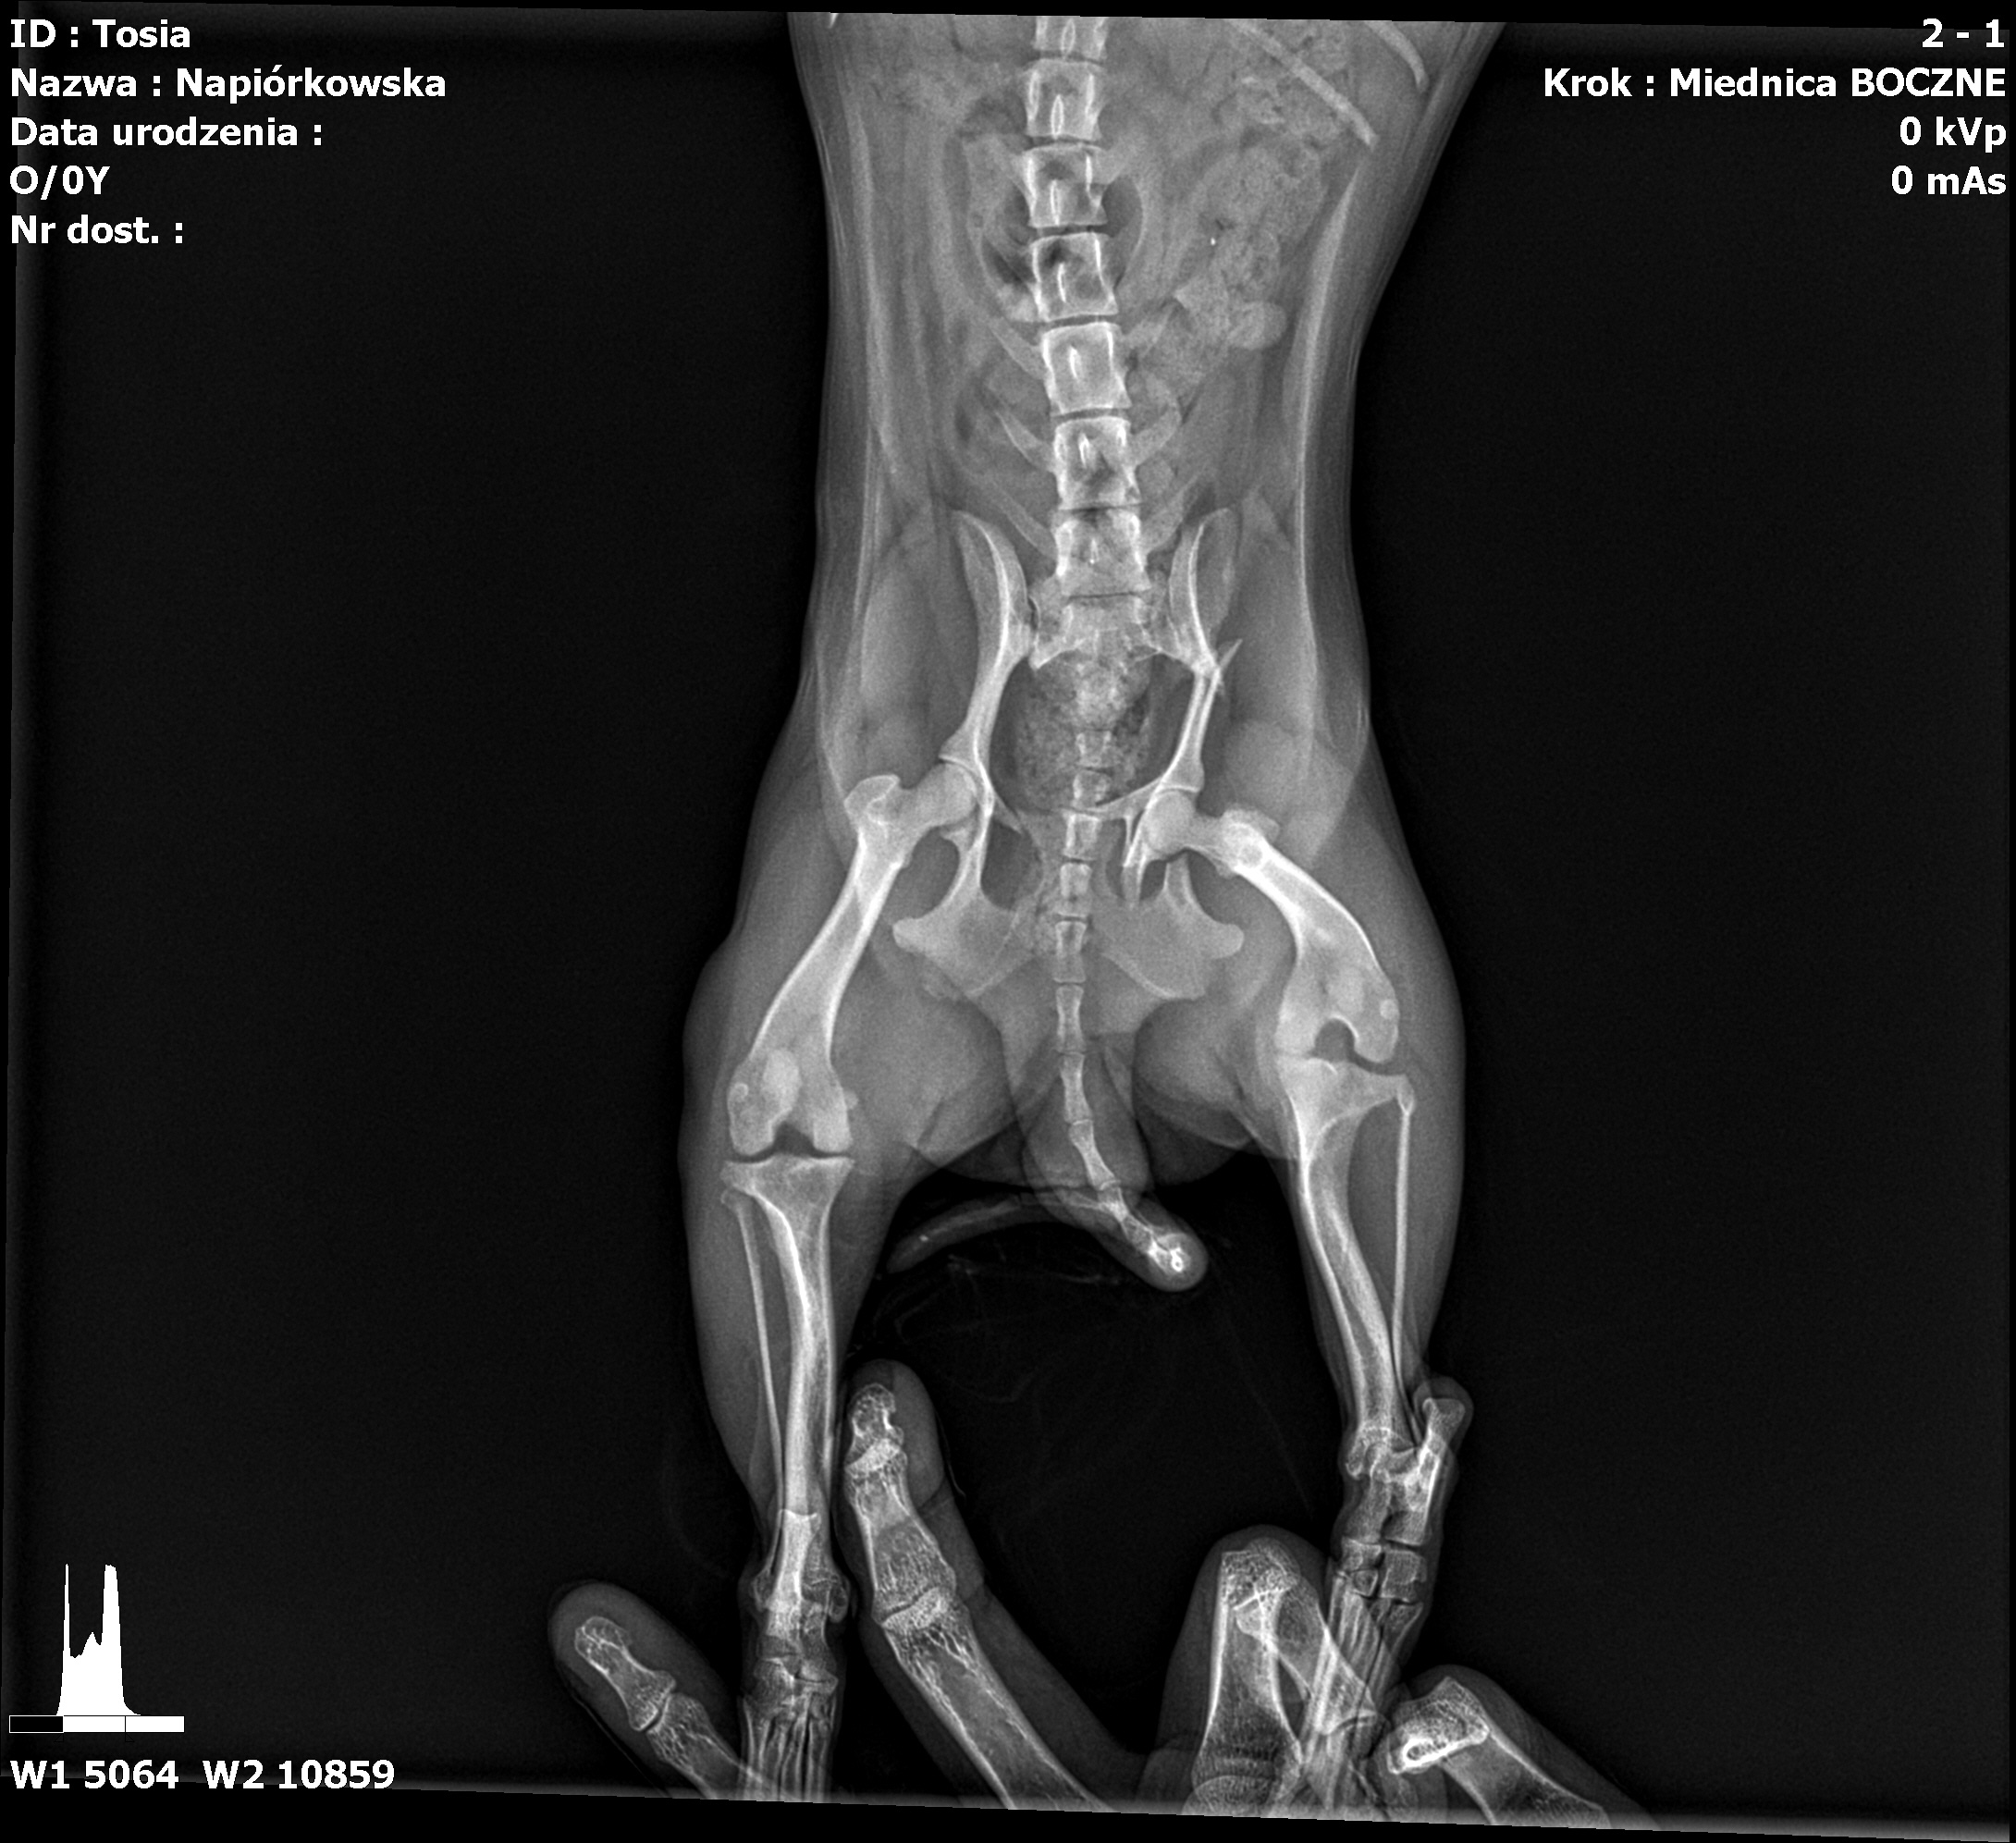

W niedzielę 12-05-2024r została potrącona. Od razu udaliśmy się do weterynarza, przebadał ja podał przeciwbólowe i przepisał kolejne. Lecz nic się nie poprawiło więc musieliśmy udać się na RTG . Niestety diagnoza nie zaciekawa bo okazało się że moja księżniczka ma złamaną kość w dwóch miejscach przy miednicy jak widać powyżej na zdjęciu. Niestety w naszej okolicy, nie wykonują takich operacji i dostałam wiadomość z punktami gdzie mogą wykonać taki zabieg i jakie idą koszty za tym.